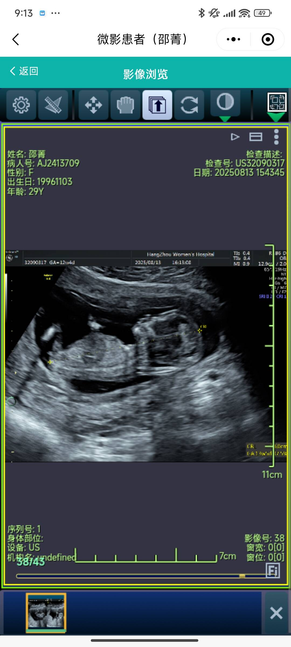

8.13 NT+无创

NT+无创!